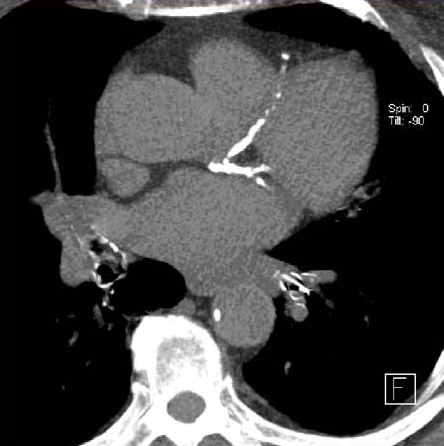

Importancia pronóstica de la determinación del calcio coronario en la TC de tórax para el rastreo de cáncer de pulmón

05 diciembre 2024

En las personas que se sometieron a una TC de tórax de baja dosis para la detección del cáncer de pulmón, la presencia de calcio en la arteria coronaria fue un predictor independiente de muerte por cualquier causa y eventos cardiovasculares, incluso después del ajuste por muerte no cardiovascular. Canadian Medical Association Journal, 2 de diciembre de 2024.